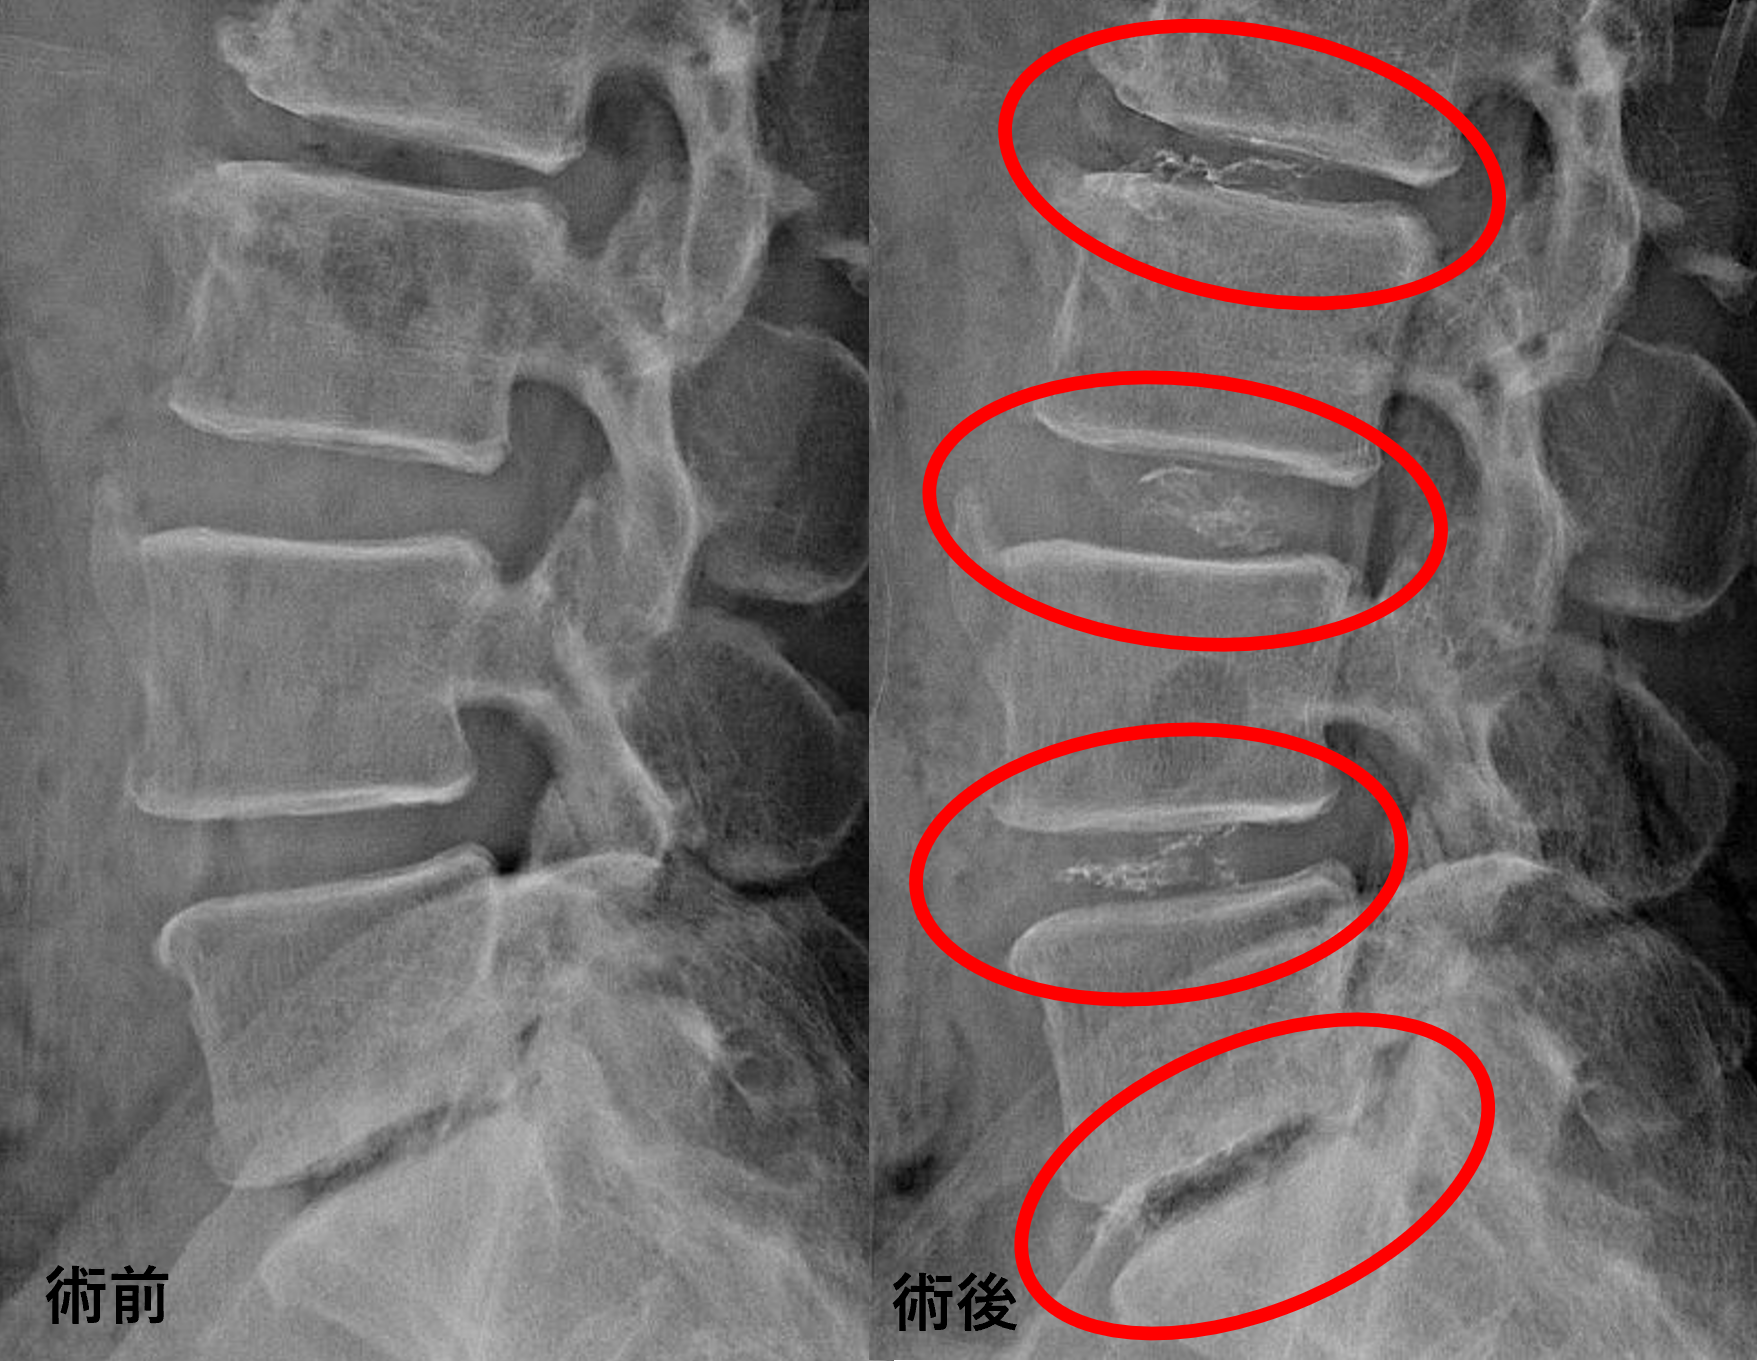

画像及び所見について

- L1/2 – 軽度椎間板変性

- L2/3 – 椎間板変性、膨隆、椎間孔狭窄、脊柱管狭窄

- L3/4 – 椎間板変性、膨隆、椎間孔狭窄

- L4/5 – 椎間板変性、椎間板ヘルニア、繊維輪断裂

- L5/s – 椎間板変性、椎間板ヘルニア、終板変性

以上のことが画像上認められました。

L2/3、3/4、4/5、5/sの椎間板所見による脊柱管の圧排が、症状の原因の可能性が高い。

患者様と相談の元、L2/3、3/4、4/5、5/sにセルゲル法を施行